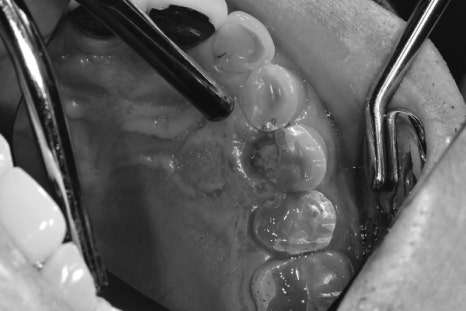

환자분을 검진을 시작해 보니 역시나 예상대로 치아가 부분적으로 파절이 되어있었고 출혈도 나오고 있는 상태였습니다.

보통 이런 상황에서 파절이 어디까지 진행되어 있는지 파악이 중요하지만 뿌리까지 진행된 경우 살릴 수는 없고 발치를 해야만 합니다.

파절 편이 뿌리끝까지 이어져있진 않았지만 파절의 경계 부분이 잇몸 깊은 곳에 형성이 되어있어 발치가 권장되는 상황이지만

환자분께서 조금이라도 본인 치아 상태에서 사용하고 싶다고 하셔서 살려서 쓰는 방향으로 진료방향을 잡게 되었습니다.